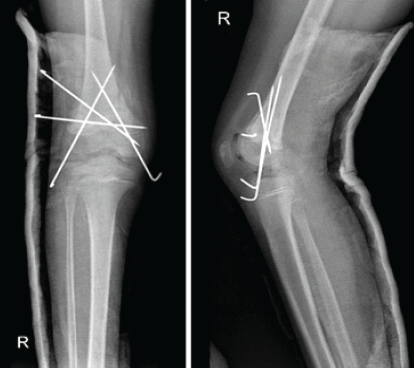

Post-operative recovery was uneventful, with the patient being discharged on day 2 of surgery after dressing and a check X-ray (Fig. 5).

Figure 5: Post-operative check X-ray – anteroposterior and lateral view.